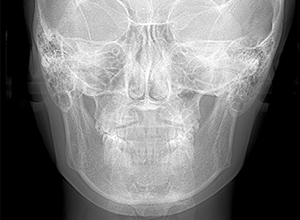

X-Ray

X-Ray所見

セファロ所見 Or-R平面からRは上方に位置づいている。中顔面部の奥行きはあるもののNasionからA点までは距離があるため、下顎は後下方へ回転している。

パノラマ所見 左右上5、左下5に歯根の湾曲が認められた。上下顎左右側8は抜去済みであった。